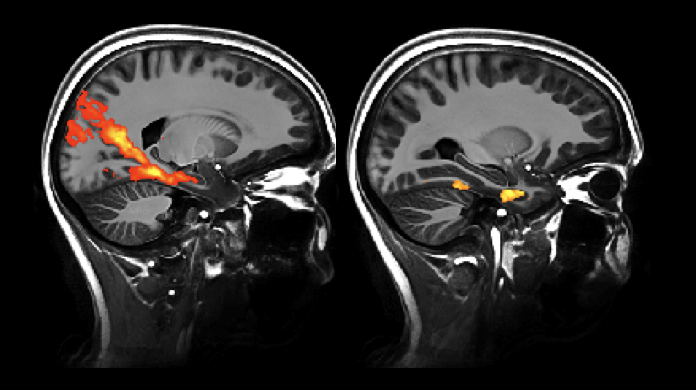

Very happy to be part of this smart study by Jenna Adams which shows that entorhinal connectivity (in young) explains the pattern of tau accumulation in old age, particulary by alEC

@tessamharrison https://doi.org/10.7554/eLife.49132 …@eLifepic.twitter.com/uXaENWjwyg